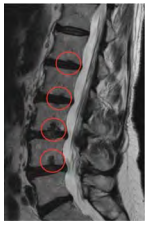

Uma paciente de 62 anos de idade apresenta dor lombar crônica recorrente, com visitas ao PS ortopédico cerca de uma vez por semana. Refere dor difusa em toda a coluna lombar. Ao exame físico, notam-se pontos miofasciais em musculatura lombar bilateral. Os testes neurodinâmicos são negativos. Por insistência da paciente, foi realizado o exame de imagem apresentado.

A respeito desse caso clínico, assinale a alternativa que apresenta a melhor conduta a ser seguida.